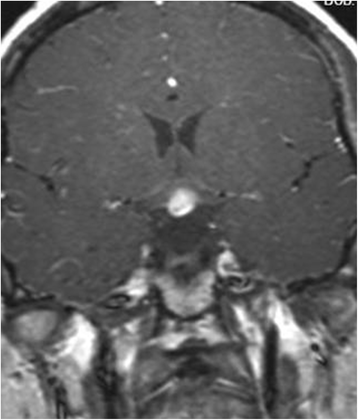

The postoperative MRI showed the lesion was disappeared (Fig. 5). However, the symptoms of polyuria and hypopituitarism were still present. Fortunately, the patient responded well to a pharmacological dose of hormonal replacement. Dose reduction resulted in exacerbation of her symptoms after one year. Finally, we decided to administer long-term hormonal replacement to control her symptoms.

The postoperative sellar MRI revealed the lesion as resolved (Fig. 10). Additionally, the symp-toms of polyuria and hypopituitarism state improved. Hormone replacement dosage was gradually diminished until she received a dose of hormonal replacement for 1 year. Symptom resolution was reported after surgery.

All eight patients had a sellar mass extending into the suprasellar region that appearing on long T1, long T2 and contrast enhanced on MRI. The lesion typically demonstrated marked, homogenous enhancement (except case 1, 2), although heterogeneous (case 2) and ring-like enhancement (case 1) was also noted. An abnormally thickened pituitary stalk was noted in all patients, and the mean size of the seller mass in our patients was 15.3 mm in the longest diameter (summarized in Table 2).

Imaging characteristically demonstrates a sellar mass with a tongue-like, suprasellar extension. The lesion may contact or infiltrate the basal hypothalamus. Pituitary stalk thickening is often a prominent feature. The lesion usually shows marked, homogenous enhancement, although heterogeneous and ring-like enhancement may also manifest. However, enhancement with contrast in granulomatous hypophysitis is very variable and it can not be used as a reliable distinguishing feature with pituitary adenomas. And other most common findings are dural enhancement and sphenoidal sinus mucosal thickening.